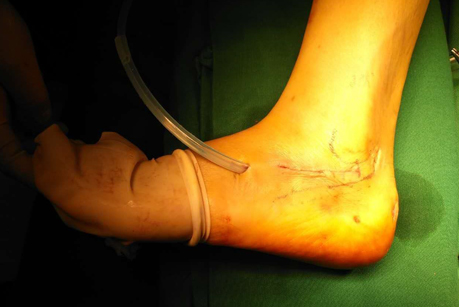

术后缝合伤口,伤口愈合,几乎看不到瘢痕